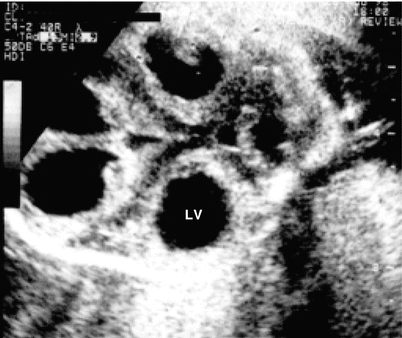

Fig. 15.5

Dilatation of the lateral ventricles (LV) observed in a cross-section of the cephalic pole at the level of the thalamus, in a fetus with toxoplasmosis